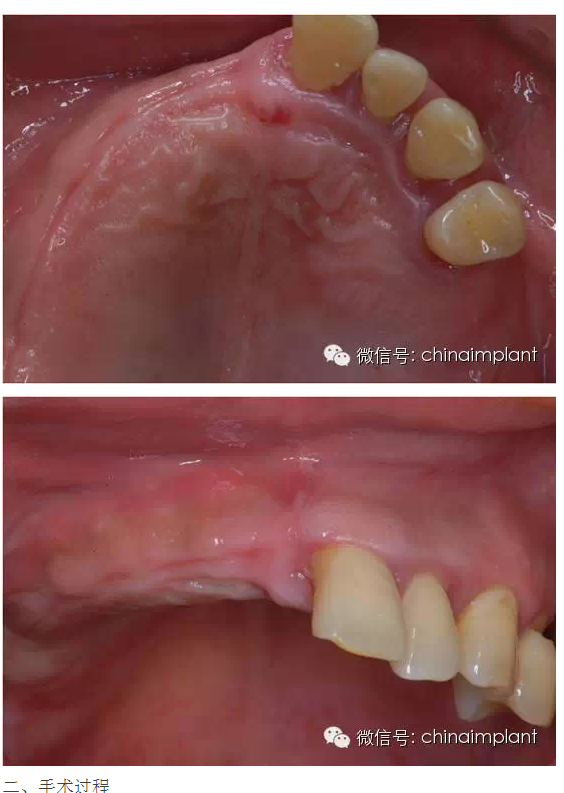

之前針對(duì)全口無(wú)牙進(jìn)行種植修復(fù)的案例中,因?yàn)轭M骨的原因,后期使用橋冠修復(fù)時(shí),一般是3部分(兩側(cè),磨牙,前牙),最近的案例中修復(fù)是一般都是做一體式的橋冠,現(xiàn)在從臨床的修復(fù)案例來(lái)看,沒有什么問(wèn)題。

此案例為術(shù)后兩周戴臨時(shí)牙。過(guò)去因?yàn)閾?dān)心感染的問(wèn)題,一個(gè)月以內(nèi)帶臨時(shí)牙也叫做即刻負(fù)重或者早期負(fù)重。(現(xiàn)在當(dāng)天戴臨時(shí)牙(即刻復(fù)重)的情況也非常常見).

本案例已經(jīng)將近10年了(2005年12月),但是修復(fù)效果個(gè)人認(rèn)為很不錯(cuò),所以拿出來(lái)和大家分享。